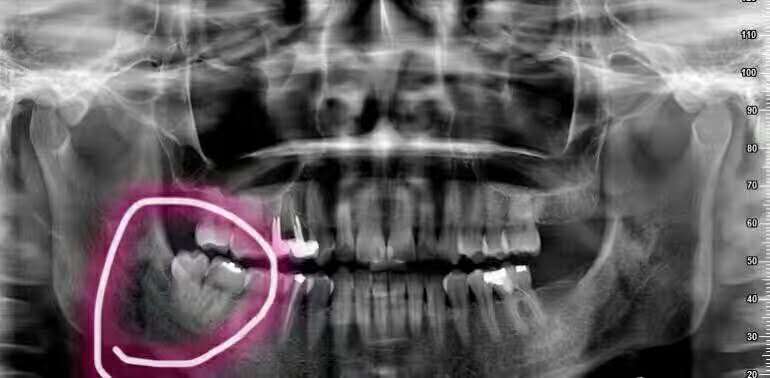

二、影响邻牙:如果生长空间不足,智齿会使劲儿顶住相邻的牙齿继续生长,可能导致邻牙损伤最后两颗牙齿都保不住。

六、阻生齿:这种类型的智齿,通常埋在齿槽骨的里面,当你感觉到痛时,就要拔掉它。